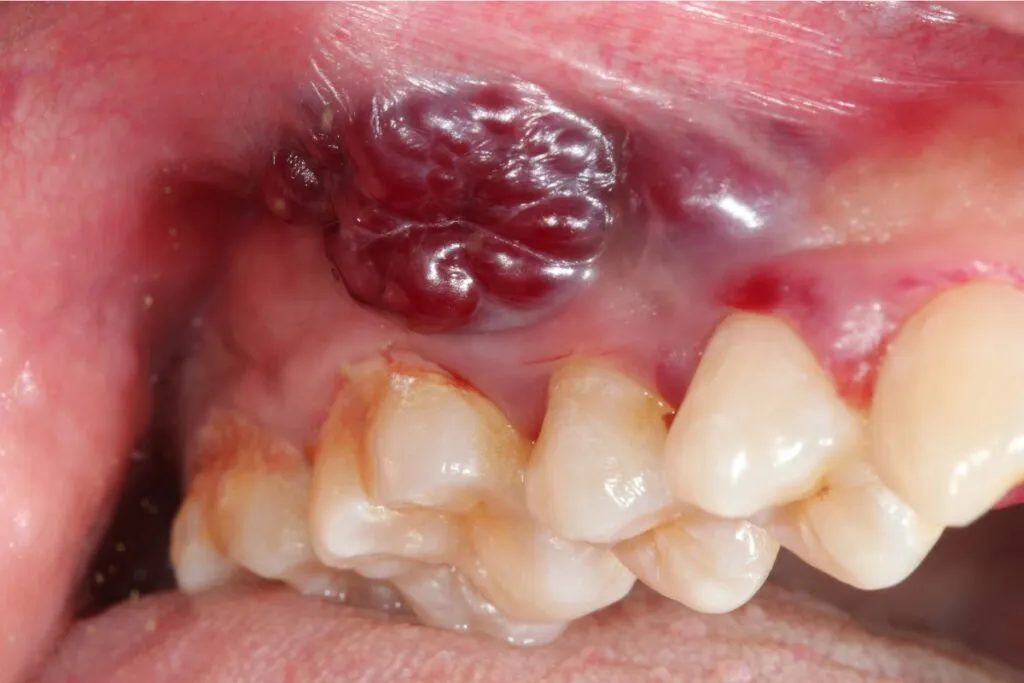

Guzek, zgrubienie, narośl: na co zwrócić uwagę na języku, dziąsłach i policzkach?

- Na dziąsłach: Nienaturalne obrzęki, guzki lub zmiany przypominające brodawkę, zwłaszcza jeśli krwawią przy szczotkowaniu.